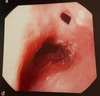

Esôfago

Câncer esofágico